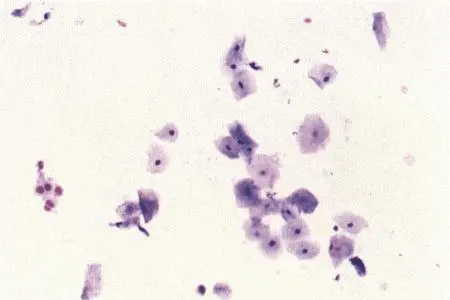

Рассматриваются следующие вопросы: нормальная физиология собак и кошек; болезни репродуктивной системы; бесплодие самок и бесплодие самцов; нормальное функционирование и дисфункция молочных желез; спаривание; искусственное осеменение; протекание беременности и роды; уход за новорожденными щенками и котятами, их наследственные и инфекционные болезни; техника оперативных вмешательств на репродуктивных органах; фармакологический контроль репродукции.